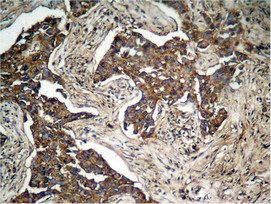

Immunohistochemical analysis of paraffin-embedded human lung carcinoma tissue, using HER2 (Phospho-Tyr1248) Antibody.